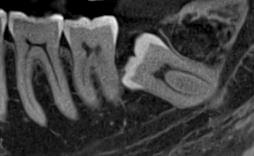

Ми розуміємо, наскільки важлива деталізація в ендодонтії та терапевтичному лікуванні.

Завдяки флагманському обладнанню PLANMECA, ми отримуємо знімки з мінімальним рівнем шумів та

високою роздільною здатністю, що дозволяє чітко візуалізувати морфологію кореневих каналів,

приховані каріозні порожнини та стан періапікальних тканин.